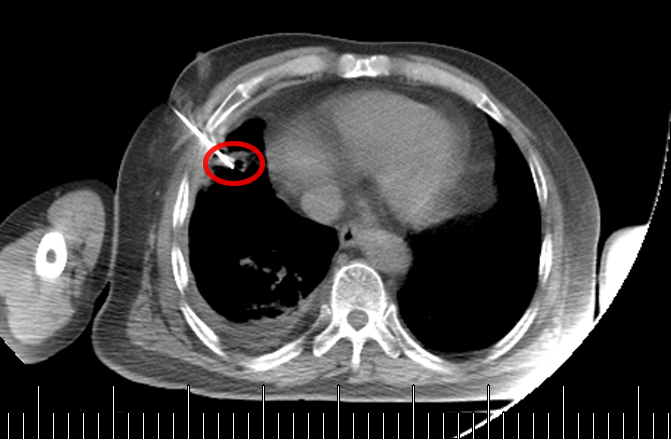

临床上曾遇到一位 80 岁的老先生,1 年多前做过结肠癌手术,病理提示为 “低分化腺癌”,术后也完成了辅助化疗。近期复查 CT 时,医生发现他的右肺门长了新东西!

从 CT 影像看,这个右肺门肿块高度怀疑是恶性肿瘤。但问题来了:老先生有结肠癌病史,这个肺肿块是新长的肺癌(原住民),还是结肠癌转移到肺部(移民者) ?

要知道,这两种情况的治疗方案截然不同,必须先明确 “肿瘤君的身份”。

起初,常规思路是做气管镜检查取病理,但完善肺功能检查后发现,老先生有重度阻塞性肺通气功能障碍(相当于呼吸系统 “交通堵塞”),根本耐受不了气管镜。好在这个肿块虽然位置特殊,但体积较大、离胸壁较近 —— 和患者及家属充分沟通后,医生决定采用 “CT 引导下经皮肺穿刺活检”。

操作很快完成,术中术后都没有出现血气胸,老先生精神状态良好,也没觉得胸闷胸痛。3 天后病理报告出来了:小细胞癌!原来这不是结肠癌肺转移,而是老爷爷患上了第二种原发肿瘤,是肺里地地道道的 “原住民”。